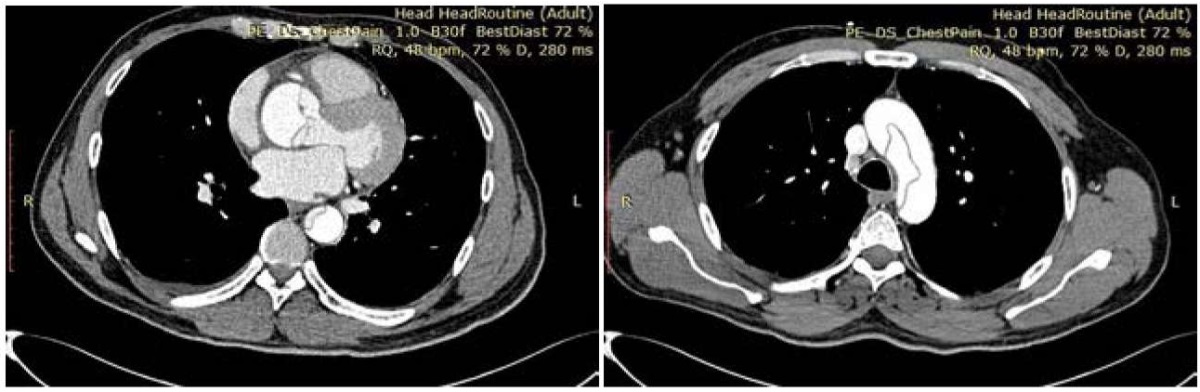

Диссекция аневризматически расширенной аорты была диагностирована при проведении эхокардиографии, были визуализированы ложный просвет и флотация отслоённой интимы. По данным ультразвукового ангиосканирования, диссекция распространялась на экстракраниальные отделу брахиоцефальных артерий с формированием стилл-синдрома слева, подвздошные артерии с обеих сторон, бедренную артерию слева. При выполнении КТ-аортографии диагноз диссекции аневризмы аорты I типа по De Bakey был подтверждён (рис. 2). При повторном исследовании патологии головного мозг выявлено не было.

Рисунок 2. КТ-аортография. Калибр восходящего отдела аорты на уровне выходного отдела левого желудочка — 31 мм, на уровне средней трети ствола лёгочной артерии — 55,5 мм, в дистальном отделе — 41 мм. На всем её протяжении от уровня корня аорты до уровня бифуркации аорты и с распространением на общие подвздошные артерии выявлен линейной формы дефект контрастирования, делящий просвет аорты на две неравные части (кпереди и справа), располагается интенсивно контрастированный и больший по объёму «ложный» просвет, кзади и слева меньший по объёму «истинный» просвет. Между «истинным» и «ложным» ходом в области аортального клапана имеется сообщение шириной до 8,3 мм.

Figure 2. CT aortography. Caliber of the ascending aorta at the level of the left ventricular outflow tract — 31 mm, at the level of the mid‑third of the pulmonary trunk — 55.5 mm, in the distal portion — 41 mm. Along its entire course from the aortic root to the aortic bifurcation, with extension into the common iliac arteries, there is a linear contrast‑filling defect dividing the aortic lumen into two unequal parts: anteriorly and to the right an intensely opacified, larger "false" lumen; posteriorly and to the left a smaller "true" lumen. At the level of the aortic valve there is a communication between the true and false lumens measuring up to 8.3 mm in width.